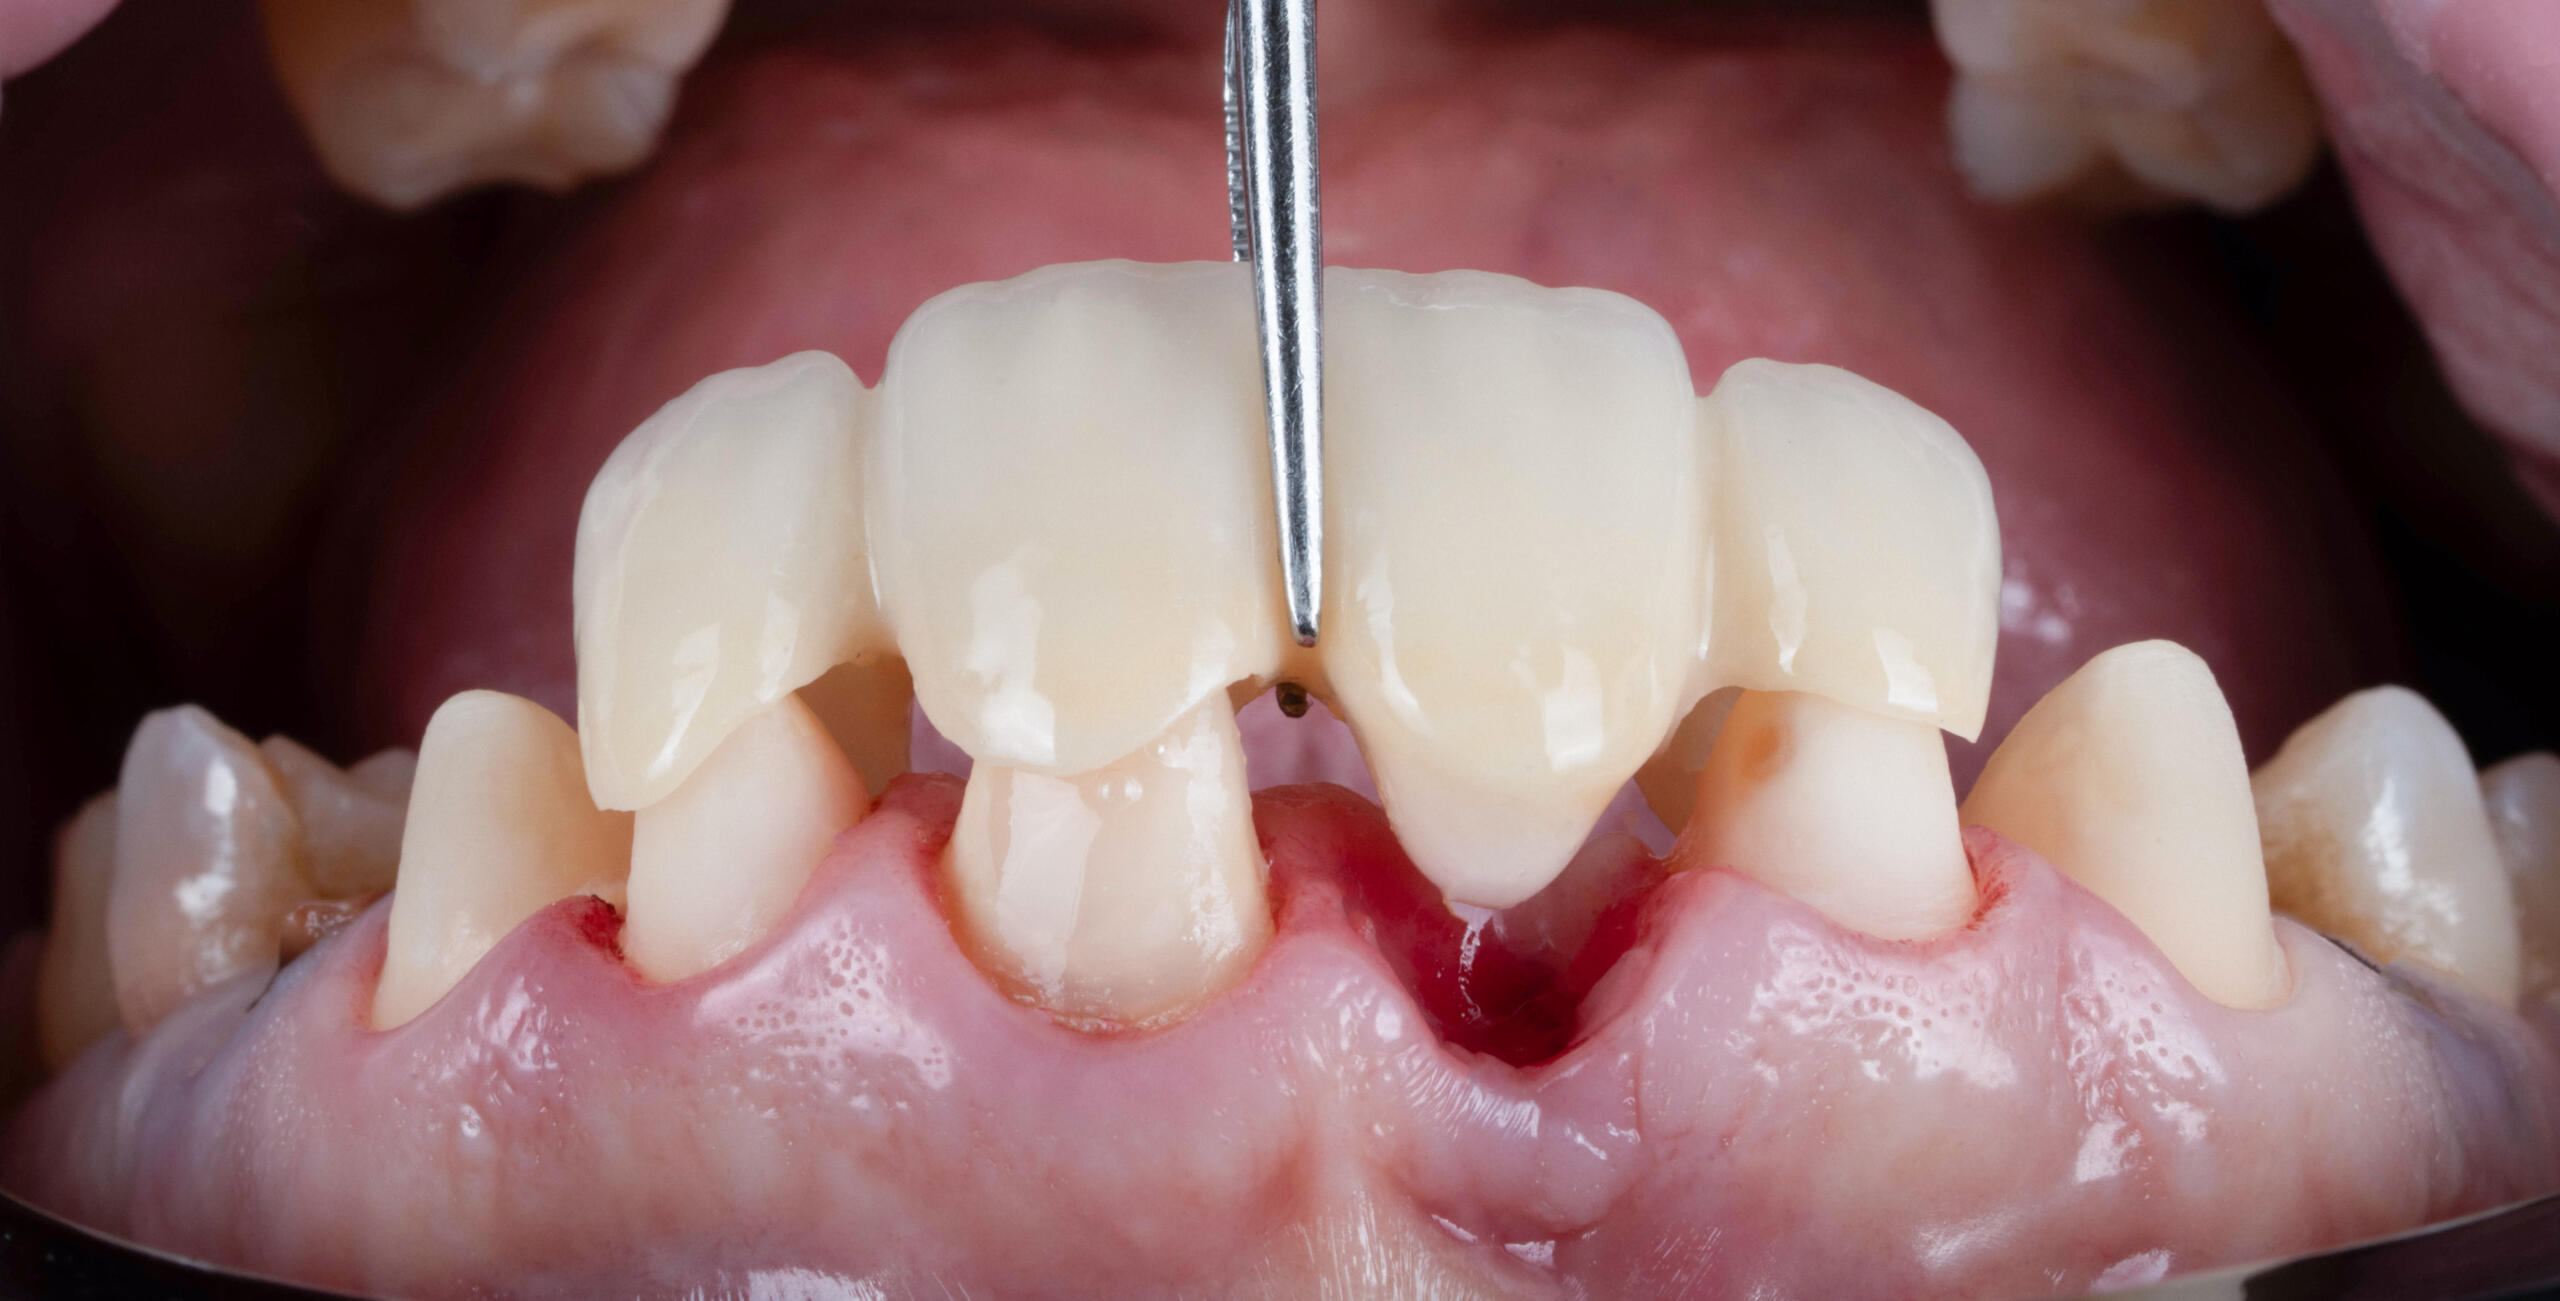

- Punte Maryland (adezivă) – fără șlefuirea semnificativă a dinților vecini; utilizată în special în zona frontală

- Proba lucrării și adaptarea funcțională și estetică